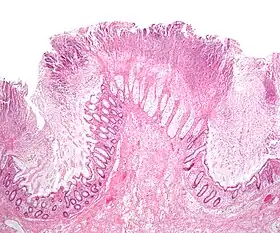

The use of systemic antibiotics, including broad-spectrum penicillins/cephalosporins, fluoroquinolones, and clindamycin, causes the normal microbiota of the bowel to be altered. In particular, when the antibiotic kills off other competing bacteria in the intestine, any bacteria remaining will have less competition for space and nutrients. The net effect is to permit more extensive growth than normal of certain bacteria. C. difficile is one such type of bacterium. In addition to proliferating in the bowel, C. difficile also produces toxins. Without either toxin A or toxin B, C. difficile may colonize the gut, but is unlikely to cause pseudomembranous colitis.[44] The colitis associated with severe infection is part of an inflammatory reaction, with the "pseudomembrane" formed by a viscous collection of inflammatory cells, fibrin, and necrotic cells.[20]

Prior to the advent of tests to detect C. difficile toxins, the diagnosis most often was made by colonoscopy or sigmoidoscopy. The appearance of "pseudomembranes" on the mucosa of the colon or rectum is highly suggestive, but not diagnostic of the condition.[45] The pseudomembranes are composed of an exudate made of inflammatory debris, white blood cells. Although colonoscopy and sigmoidoscopy are still employed, now stool testing for the presence of C. difficile toxins is frequently the first-line diagnostic approach. Usually, only two toxins are tested for—toxin A and toxin B—but the organism produces several others. This test is not 100% accurate, with a considerable false-negative rate even with repeat testing.[46]

Pseudomembranous colitis first was described as a complication of C. difficile infection in 1978,[110] when a toxin was isolated from people with pseudomembranous colitis and Koch's postulates were met.